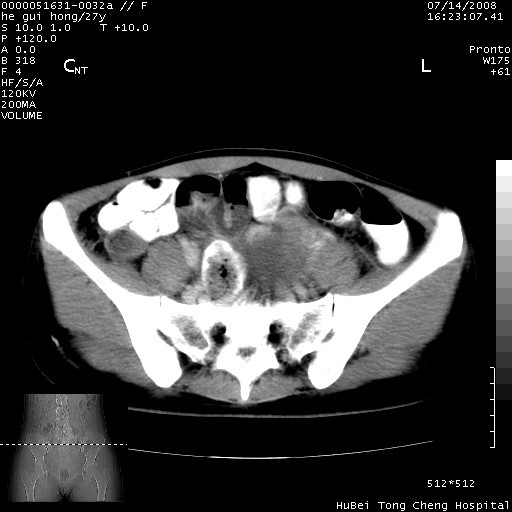

以下是引用杀毒软件在2008-7-20 8:03:00的发言:[br]支持双侧卵巢囊腺瘤可能性大!

以下是引用zjzjr在2008-7-20 13:36:00的发言:[br]双侧附件囊腺瘤可能性大!